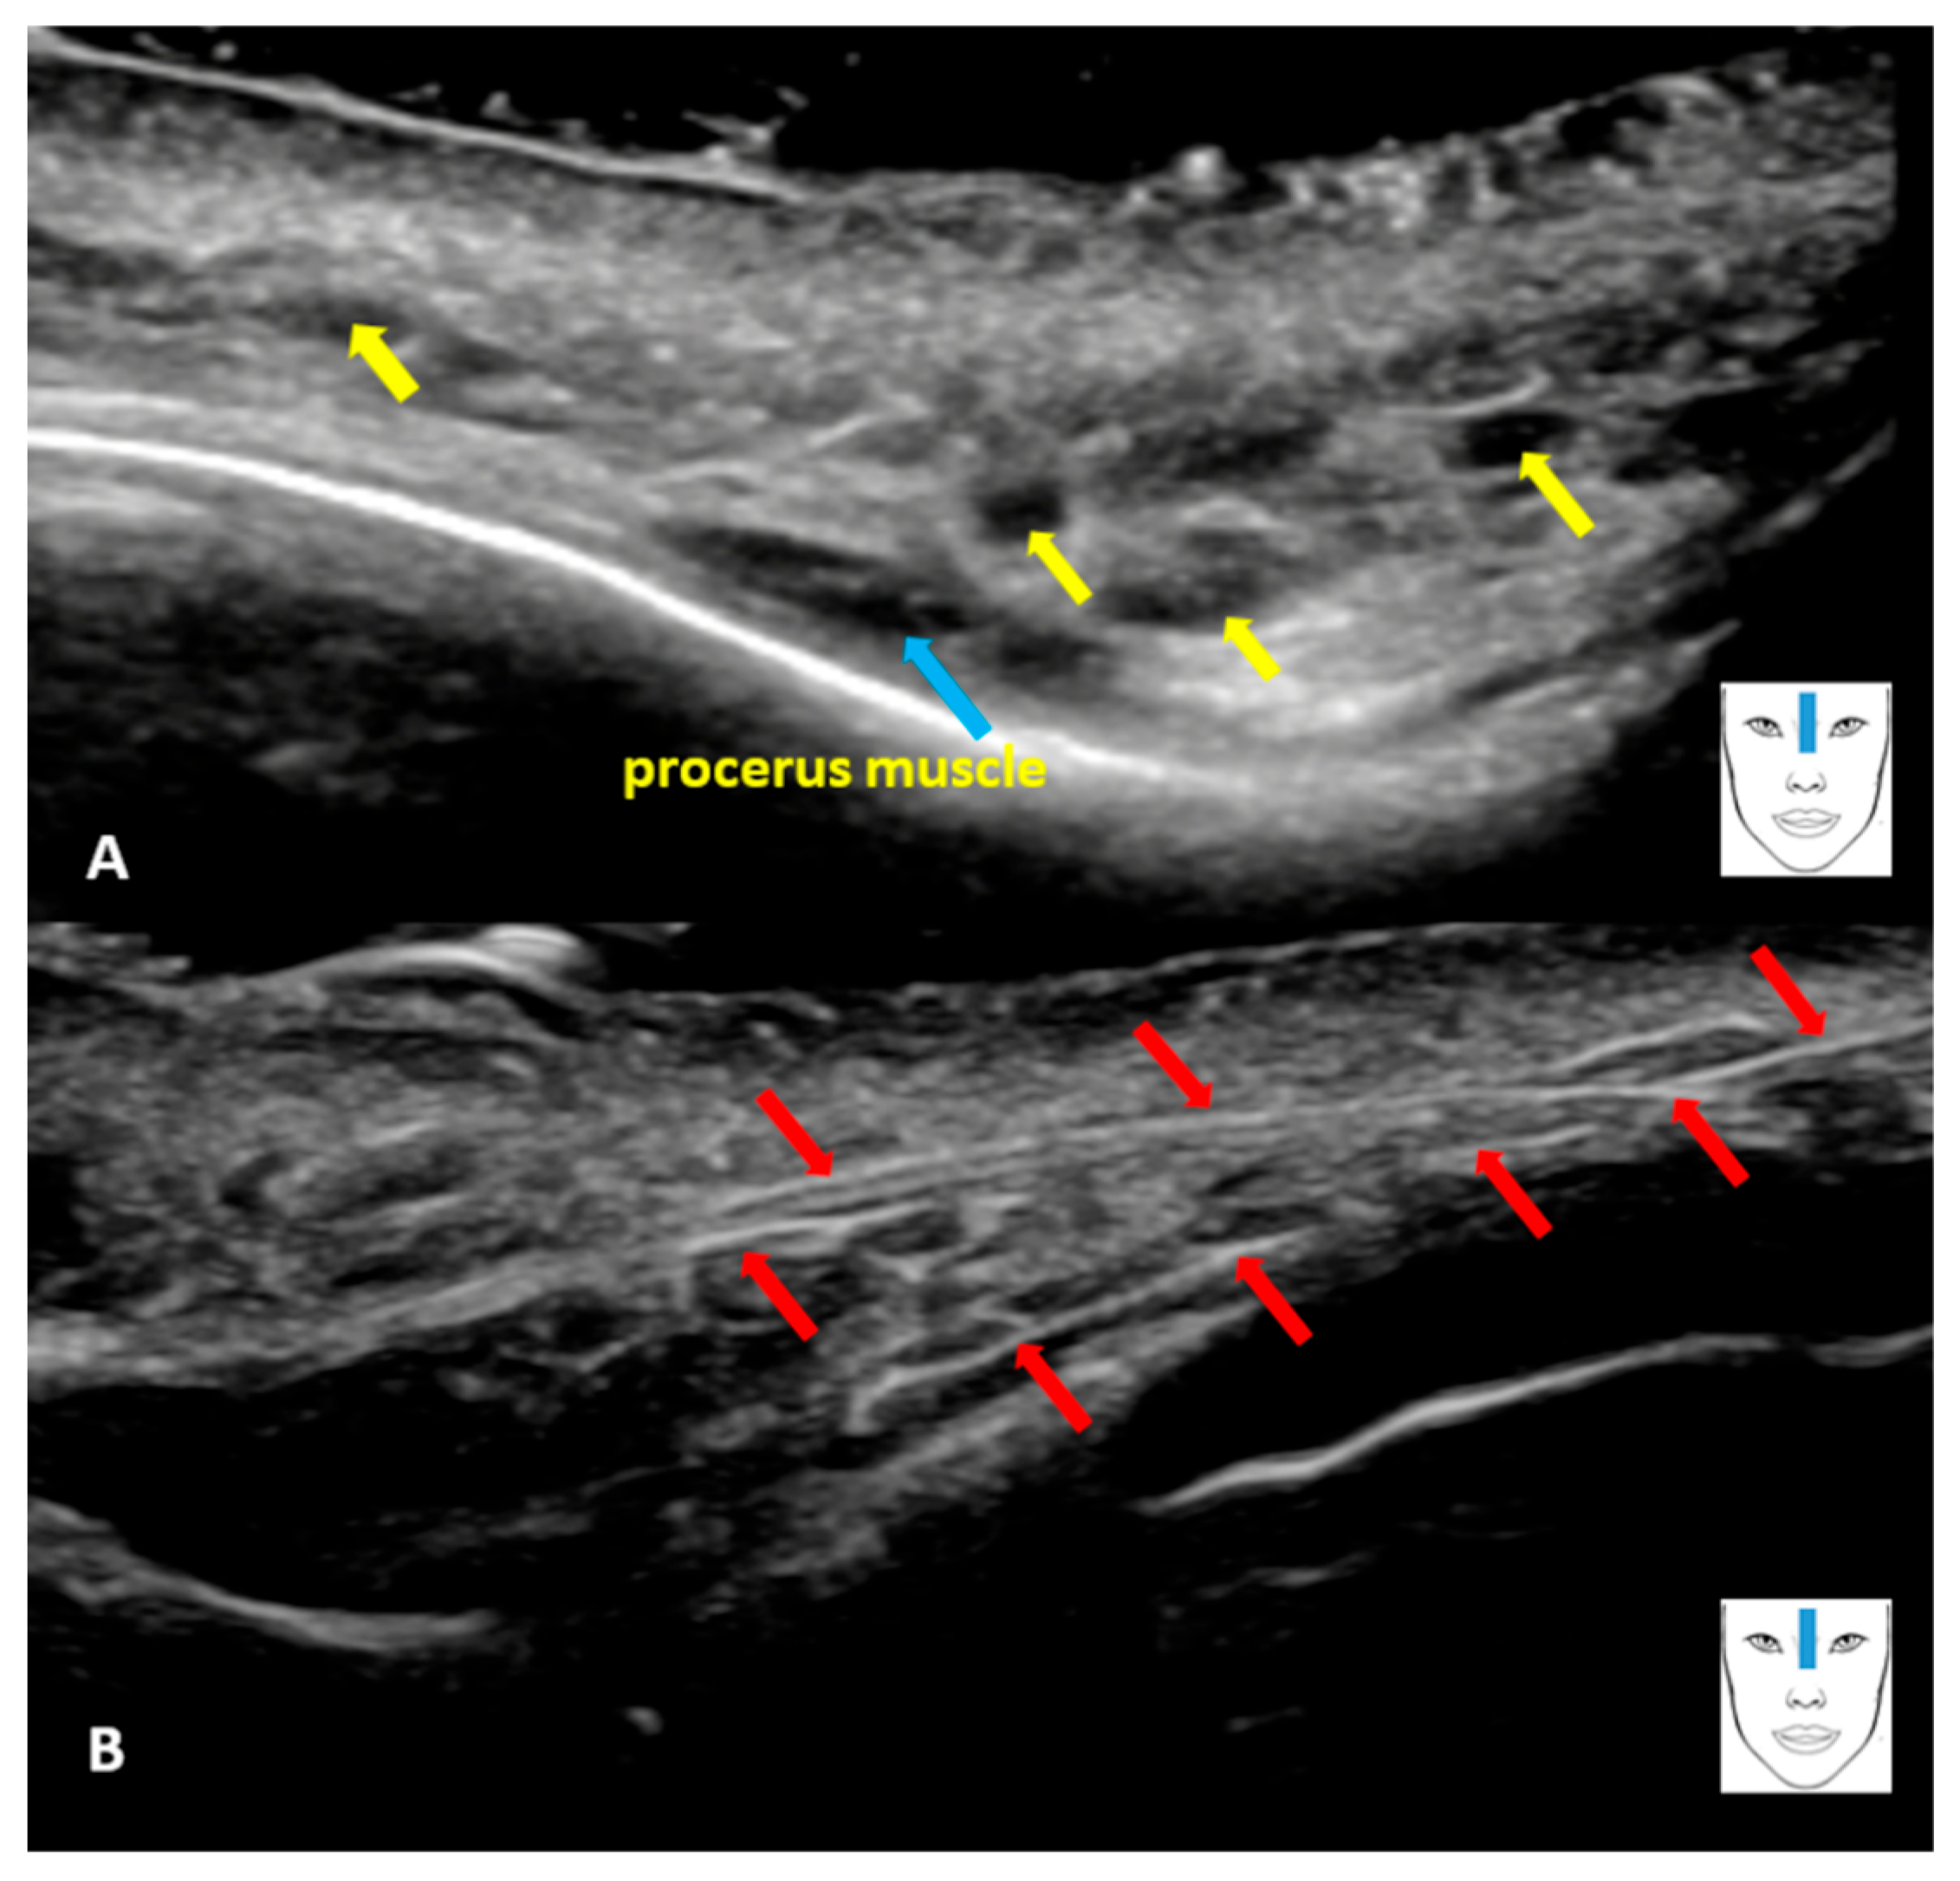

The Usefulness of High-Frequency Ultrasound in Assessing Complications After Minimally Invasive Aesthetic Medicine Procedures, Using the Example of Assessing Blood Flow in the Dorsal Artery of the Nose

Mlosek, R.K. The Usefulness of High-Frequency Ultrasound in Assessing Complications After Minimally Invasive Aesthetic Medicine Procedures, Using the Example of Assessing Blood Flow in the Dorsal Artery of the Nose. Diagnostics 2026, 16, 271. https://doi.org/10.3390/diagnostics16020271